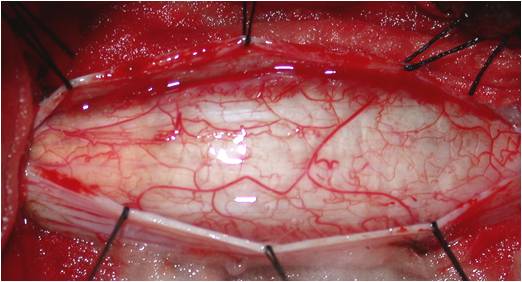

硬膜切开,见脊髓肿胀